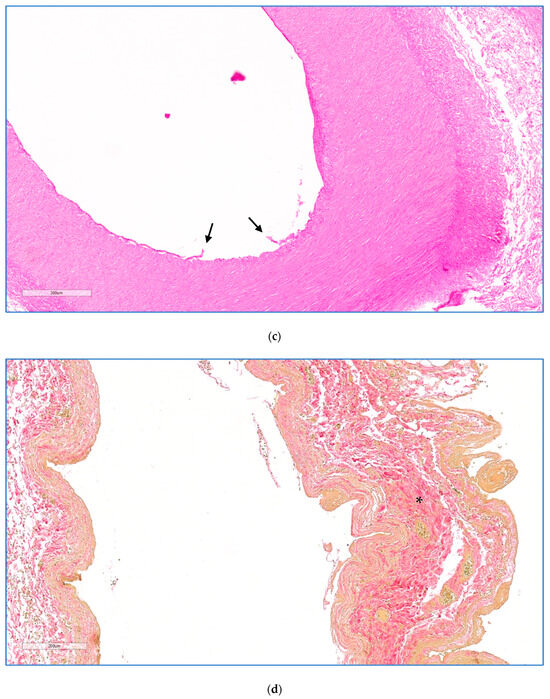

On microscopic examination, areas of coagulative necrosis were seen in the pancreas of all animals, except animal 3. These were often patchy and sometimes more extensive, particularly in the animals that had received the higher drug doses. An overview of the entire treated area of animal 5 treated at a dose of 0.8 mg·kg−1 is shown in Figure 4a. The distance in mm between the outer edge of the treated vessel and the zones of necrosis in the tissue from each animal was measured (Table 1). At high magnification, the interface between necrotic and morphologically viable tissue was identified as a distinct line (Figure 4b). No definite evidence of necrosis was seen in the pancreas of animal 3, treated at the lowest drug dose.

Figure 4.

(a) Histology of animal 5 treated at a dose of 1.6 mg·kg−1. Showing an H&E image with a low-magnification overview (3 mm scale) encompassing the treated splenic vein, splenic artery, a necrotic margin of perivascular necrosis extending into the pancreas, and a sharply demarcated necrotic zone boundary (dotted line), beyond which the pancreatic parenchyma is normal. The perivascular necrotic zone was characterised as having patchy necrosis of pancreatic lobules, with associated cytosteatonecrosis extending into the septa, microthrombosis, haemorrhage, and abundant inflammation rich in neutrophils and macrophages. Higher magnifications of the artery, vein, and pancreas are shown in (b–d). (b). High power image of pancreas showing sharp demarcation (dotted line) between necrotic pancreatic tissues on the left (resulting from EPA) and viable pancreas on the right (H&E, scale 200 μm). (c) High power image of the splenic artery (animal 2) showing severe, extensive necrosis of the endothelial lining, endothelial cell detachment (arrow), endothelial cell degenerative change, and marked degeneration of the deep layers. (HE, scale 200 μm). (d) High power image of a treated splenic vein, showing collagenisation of the wall (*), with atrophy of the muscular media, and mild transmural inflammatory infiltrate associated with focal ulceration of the endothelium (EVG, scale 200 μm).

3.5. Histopathological Examination of Blood Vessels

Full-thickness effects were seen in the walls of all vessels examined 2 days after treatment. Microscopic examination of hematoxylin and eosin (H&E) and Elastic Verhoeff Van Gieson (EVG) stained sections was performed (I.A.S.) to evaluate the morphology of the vessel wall (integrity, aspects of the media and endothelium) and the extent of the perivascular pancreatic tissues undergoing necrosis. The results are listed in Table 1. In all animals, except for the one treated at the lowest dose, the endothelium displayed reactive change, erosion/ulceration, or detachment from the basal membrane. The vessel wall showed necrotising arteritis, leading to a thickened intima with atrophic media in the treated veins, as illustrated in the higher magnification views in Figure 4c,d. There was some alteration of the collagen structure in treated arteries, but no loss of integrity. Perivascular oedema and congested vasa vasorum were also noted. In animal 1, sacrificed 1 day after treatment, luminal arterial defects (focal extensive necrotico-neutrophilic arteritis) and splenic artery obstruction were observed within the irradiated vessel segment, thought to have their traumatic origin due to the extensive endovascular catheter manipulation and balloon over-distension. No compromising effect was observed on the extracellular matrix (ECM) that makes up the integrity of the vessel wall.